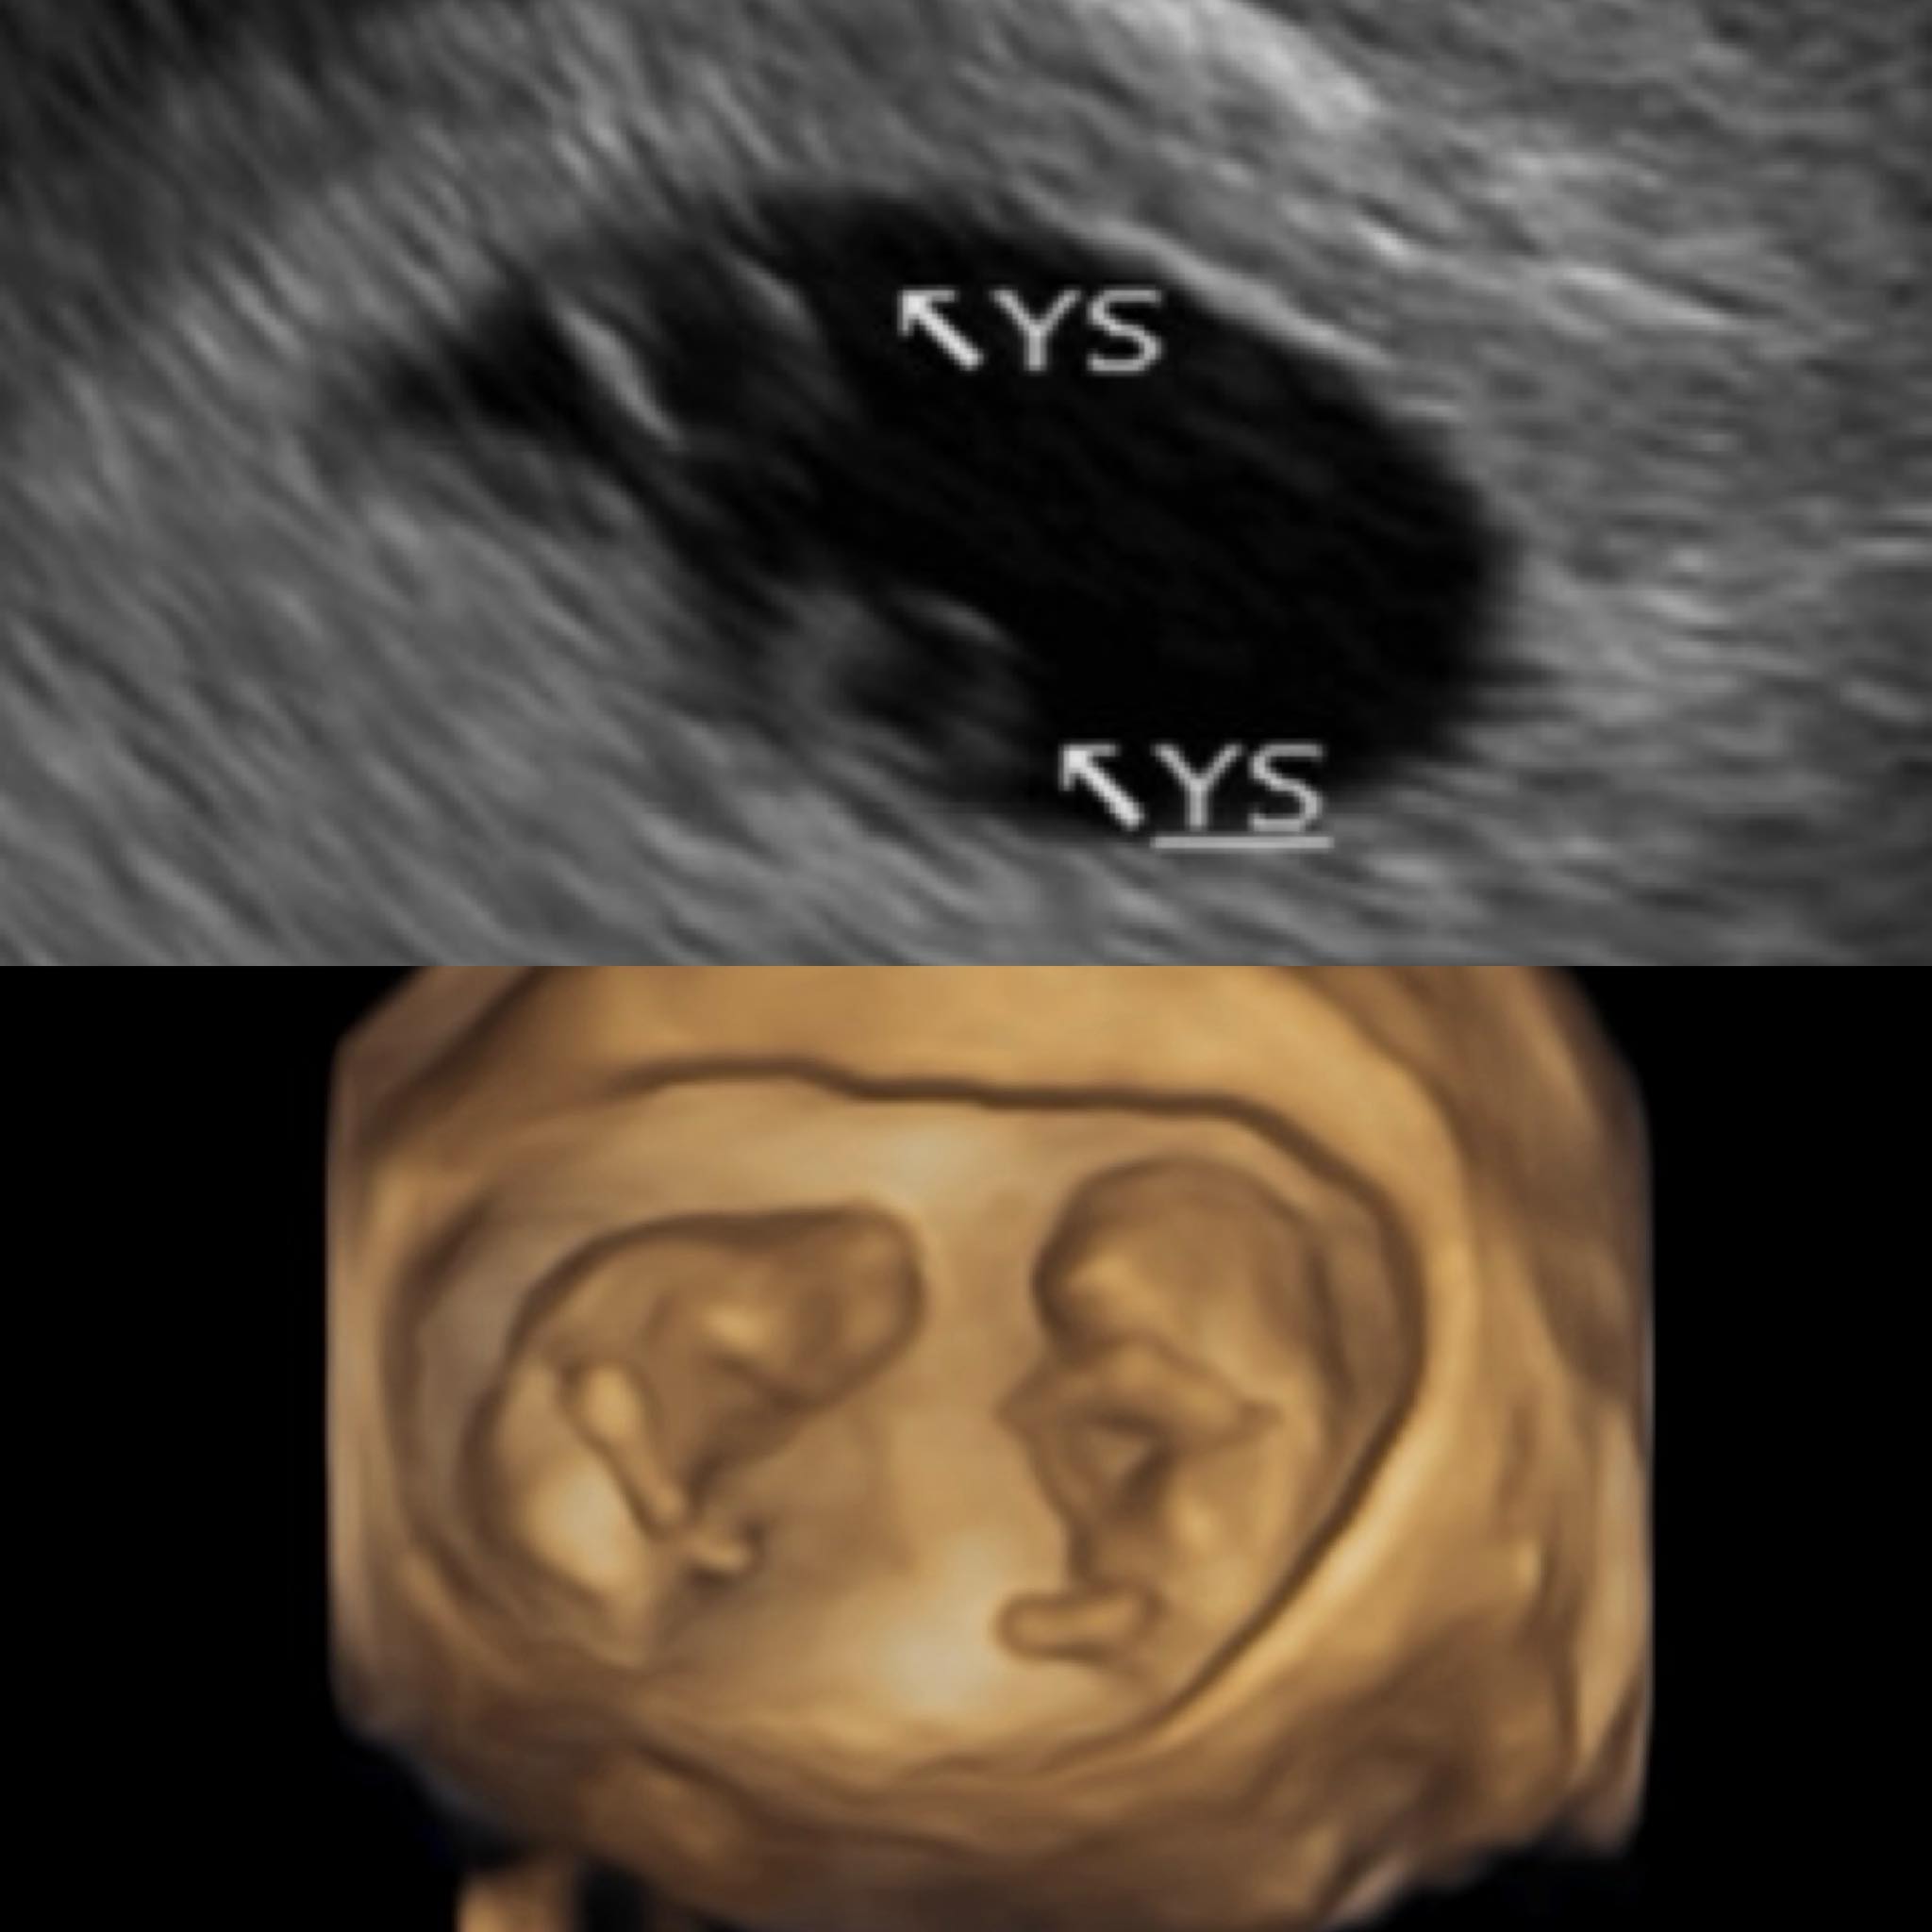

藝人鄭家純(雞排妹)在日前宣布懷孕12週的好消息,肚子裡正孕育一對同卵雙胞胎,預計將在10月底、11月初生產。令人驚訝的是,她其實去年底才懷孕過一次,但因為胚胎在早期就停止發育,今年1月初被迫中止妊娠,怎料小產還不到1個月,竟就又順利懷上雙胞胎!